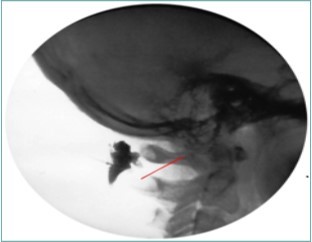

Because of the proximity to the vertebral artery and the potential risk of intravascular injection, few interventionalists have been interested in AA injections, and, since the proximal GON travels over the posterior arch of the atlas, even fewer have been interested in direct injections of the proximal GON. In an effort to avoid the “locked-in” syndrome complication seen with occipital injections, Dr. Gabor Racz developed a suboccipital approach to the suboccipital space in 1982, which has recently become more popular7, 8. A curved, bullet-tipped needle with side port injection, attached tubing, and wings (dubbed the “Stealth needle”™ because of its resemblance to the Stealth bomber) Figure 5 is used to approach the suboccipital triangle from above. Since the underlying pathology is usually bilateral, the procedure is usually performed bilaterally.The patient is positioned prone on the fluoroscopy table, with the neck in flexion; the hair is pulled cephalad, and the suboccipital area is sterilely prepped and draped. The inion and conjoined tendon are identified by palpation and the nuchal line is identified by fluoroscopy; the entry site should be 2cm lateral to the midline on the nuchal ridge. After making sure by palpation that the planned entry is not directly over the occipital artery, a small skin wheal of local anesthetic is injected via a 30g needle. Because the galea is so strong, an 18g needle is used to create a small stab incision in the scalp and deep fascia to facilitate the entry of the blunt-tipped needle. Standing at the head of the bed, the Stealth needle is held by the wings like a butterfly IV needle, and, with tip facing down and toward the feet Figure 6 the needle is advanced caudally. The needle position is initially identified on an anterior-posterior fluoroscopy view, with the target medial to the superior pars of C2 Figure 7 The needle is advanced through the muscle and fascial layers of the trapezius and semispinatus with confirmation of location on lateral view, aiming for the superior lamina of C2 at the level of the spinous processes Figure 8. Contrast is injected to verify needle placement Figure 9 followed by 10 cc of local anesthetics and steroids (4.5ccs 0.2% ropivicaine, 4.5ccs 1% lidocaine, and 10mg of dexamethasone on each side) to perform an adhesiolysis, freeing up the greater occipital nerves Figure 10 Because this technique is usually performed bilaterally, lower concentrations of local anesthetic are used to avoid toxicity issues.

Figure 9.Lateral Fluoroscopic image showing initial contrast location deep to the suboccipital muscles; red line corresponds to the level of the inferior oblique capitus muscle. (Image courtesy of Gabor Racz, MD)